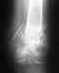

Мне 43 года. 08.01.12 была травма: перелом малой берцовой кости и разрыв межберцового синдесмоза. В тот же день была прооперирована:установлена пластина с 6 отв. + позиционный винт синдесмоза.Через 7 недель винт был извлечен и разрешена полная нагрузка ноги. На осмотре 18.05.2012 был определен посттравматический артроз голеностопа и предложена операция. Врач настаивал на её срочном проведении, но я в силу ряда причин могла оперироваться только в конце лета.Когда же я пришла договариваться о госпитализации в конце августа, то врач сказал, что он стоит перед диллемой: стоит ли её делать...Сустав компенсирован, болей нет, сращение произошло хоть и неправильное, но прочное. Связки зарубцевались. Преложил даже усилить нагрузку на ногу с целью выявления скрытых симптомов. И даже не исключил катание на лыжах грядущей зимой!Я не вполне поняла: все хорошо или наоборот, необратимо??? Стоит ли настаивать на операции (было сказано, что она может и ухудшить состояние).Нога практически не болит. Щиколотка увеличена по сравнению со здоровой на 5 см, не отечна. Но ограничена в движении (спускание по ступеням, приседания...)Врач вызывает у меня однозначное доверие. Он оперировал и консультировал (успешно) многих моих знакомых. Знаю о нем, как о порядочном человеке. Что бы вы посоветовали? Заранее благодарна за ответ.